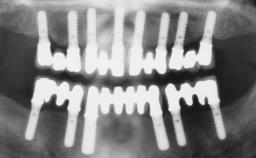

Transition from an “irrational to treat” Maxillary Dentition to a Full-Arch Segmented FDP by Early Loading of Eight Implants Placed Using the Staged Approach

The staged approach permits the transition from an “irrational to treat”dentition to a full arch implant supported restoration without any need to use a removable provisional prosthesis or to apply the immediate-placement and immediate-loading techniques. A failing dentition is the usual indication for a staged treatment. On the other hand, the dentition should still contain many residual teeth, but with few or none of them being suitable for use as definitive abutments for a full-arch fixed restoration.This situation is usually the result of advanced periodontal disease or of the failure of an extensive fixed prosthesis.